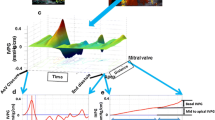

Measurements of intra- and inter-ventricular dyssynchrony

For the assessment of intra- and inter-ventricular dyssynchrony (Fig. 1), both systemic RV and pulmonary LV in the short-axis, and four-chamber cine images were assessed using a feature-tracking method Vitrea (Canon Medical Systems Corporation, Otawara, Japan). The systemic RV in the short-axis of the mid-ventricular level, and at the four-chamber view, was divided into six segments. The intraventricular dyssynchrony time was defined as the maximum difference between the peak times of septum and systemic RV free walls. The interventricular dyssynchrony time was defined as the maximum difference between the peak times of the biventricular free walls.

Feature tracking on CMR. Intraventricular dyssynchrony: systemic RV at the four-chamber was divided into 6 segments. The intra-ventricular dyssynchrony time was defined as the difference between the peak times of septum and systemic RV free wall. White line showed longitudinal global strain. Interventricular dyssynchrony: both RV and LV were considered as a single heart and the interventricular dyssynchrony time was defined as a difference between the peak times of biventricular free walls